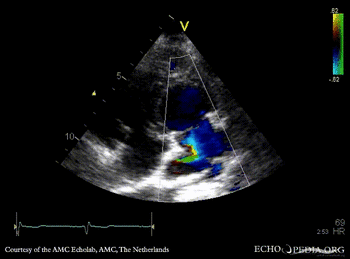

E00576.gif E00577.gif

PLAX: dilated coronary sinus PLAX with Color Doppler: pulmonary vein drainage into coronary sinus, connection with left atrium